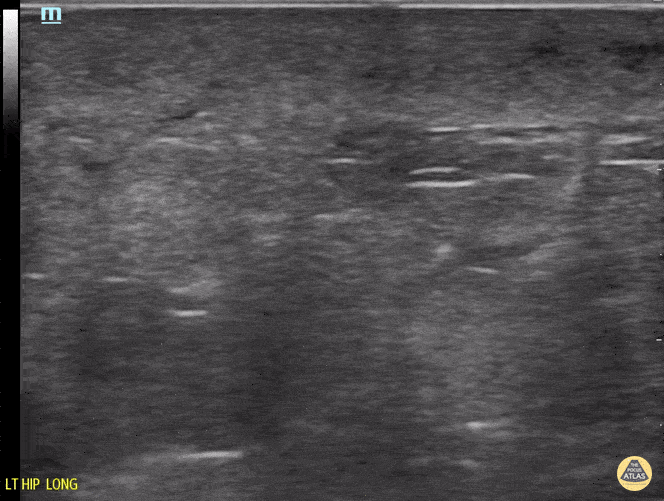

Hip cellulitis in a teenage female patient. Contributor: Jaron Smith, MD, Phoenix Children's Hospital